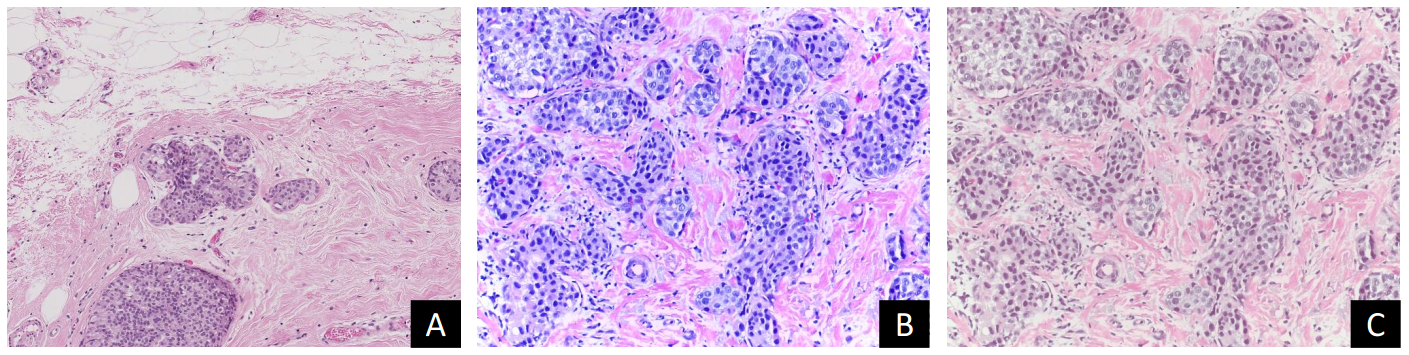

Refer to caption

Figure 2: Output of stain normalization: A, B and C show the target image, the original image and the stain normalized version of B respectively.